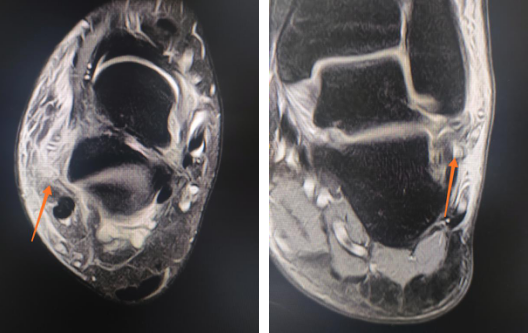

男生蹦下楼梯右踝骨折,踝关节镜下微切口复位骨折修复韧带

患者15岁,蹦下楼梯时扭伤右脚踝,导致右外踝骨折,右外踝关节侧副韧带断裂。

2020年9月,sararz足踝科二病区徐明亮主任团队采用踝关节镜为这名右踝骨折的初中男生进行了关节镜下骨折复位内固定、韧带修复踝关节稳定术,手术很顺利,术后第四天,男生就出院回家休养。

踝关节镜技术相对开放手术的特点很明显:1、小切口,瘢痕小,周围组织损伤轻;2、镜下观察的踝关节范围大;3、恢复时间短,早期行康复锻炼。

韧带受伤

右外踝骨折(左),术中(右)